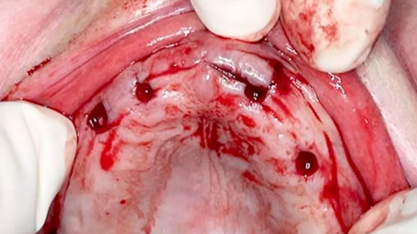

拔除殘根(圖 4),將導(dǎo)板完全覆蓋在黏膜上(圖 5),環(huán)切黏膜瓣(圖 6)

(圖4)

(圖5)

(圖6)